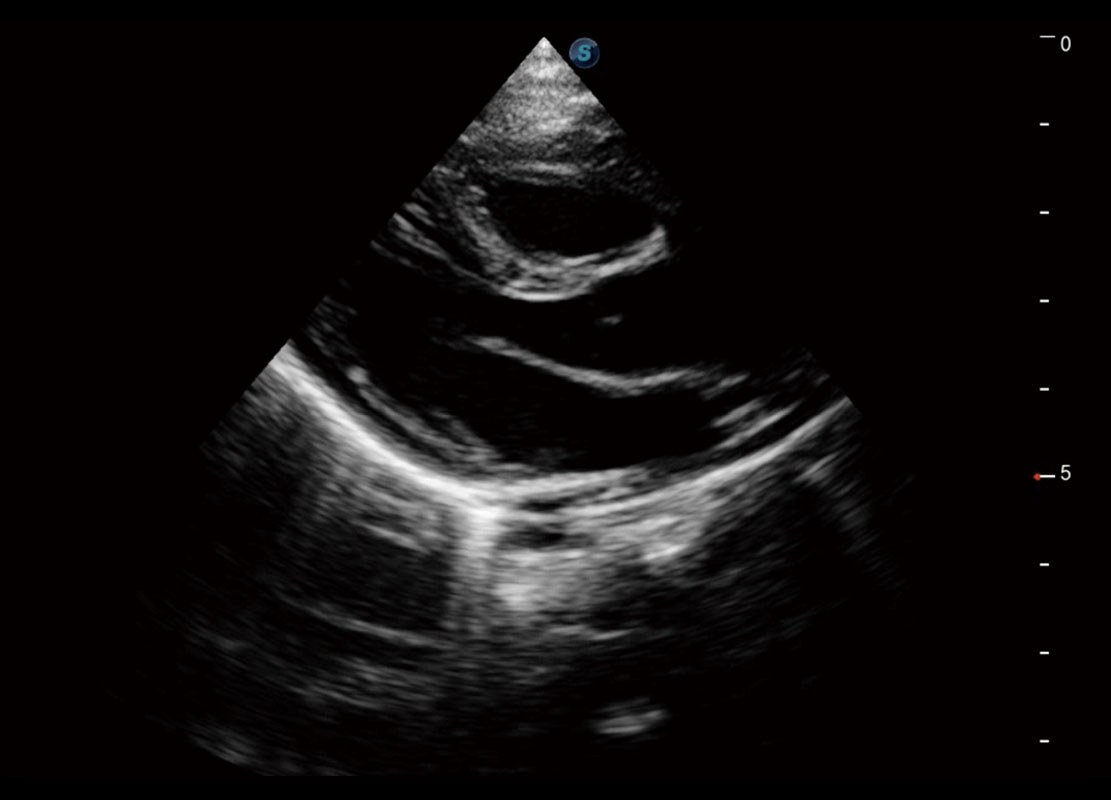

右室双出口